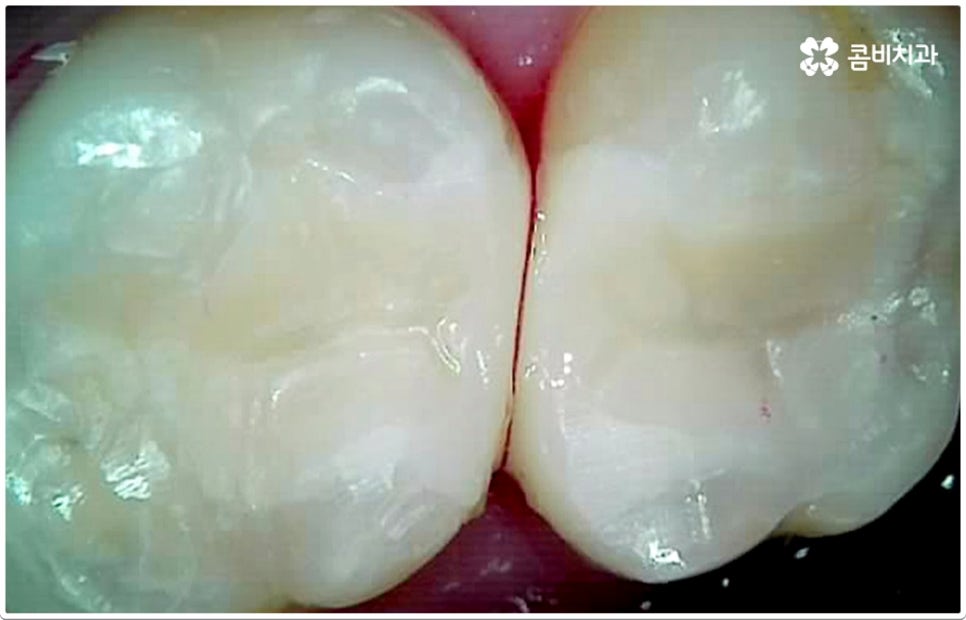

충치의 원인이 되는 세균이 급격하게 증식하게 되는 온상인 치석은 치아와 치아 사이, 또는 치아와 잇몸 사이에 플라그와 음식물 찌꺼기가 엉겨붙어 딱딱하게 굳은 것이라서 칫솔질로 제거되지 않기 때문에 주기적인 스케일링 치료를 통해 물리적으로 떼어낼 필요가 있어요. 또한 초기 충치 또는 치아사이충치 같은 경우 환자분들의 입장에서 바로 발견하는 것이 어려울 수 있기 때문에 혹시 자신이 모르는 사이에 충치가 진행되고 있지는 않은지 꼼꼼하게 살펴보고 빠르게 대처할 수 있도록 하기 위해 1년에 한 번 또는 두 번 정도 치과에 내원하셔서 정밀 검진을 받으시길 권유드리고 있습니다.

게다가 치아사이충치 는 두 치아의 인접면에 발생하여 한꺼번에 두 치아에 손상을 주기 때문에 보다 빠른 대처가 필요한데도 불구하고 말씀드린 것처럼 발견하기도 쉽지 않을 뿐더러 음식을 저작하는 치아의 교합면 (위아래 맞물리는 면) 에 생기는 충치가 아니기 때문에 수직으로 우식 부분까지 파고 내려가는 치과 충치 치료 기구들의 특성상 접근하기가 용이하지 않아 까다로운 진료에 속한다고 할 수 있어요. 특히 환자분들의 치아사이충치 발병 상황에 따라 치료 과정에서 부득이하게 삭제해야 하는 치아량이 생각보다 많아지는 케이스가 있을 수 있으므로 이에 대해 잘 알아두실 필요가 있습니다.